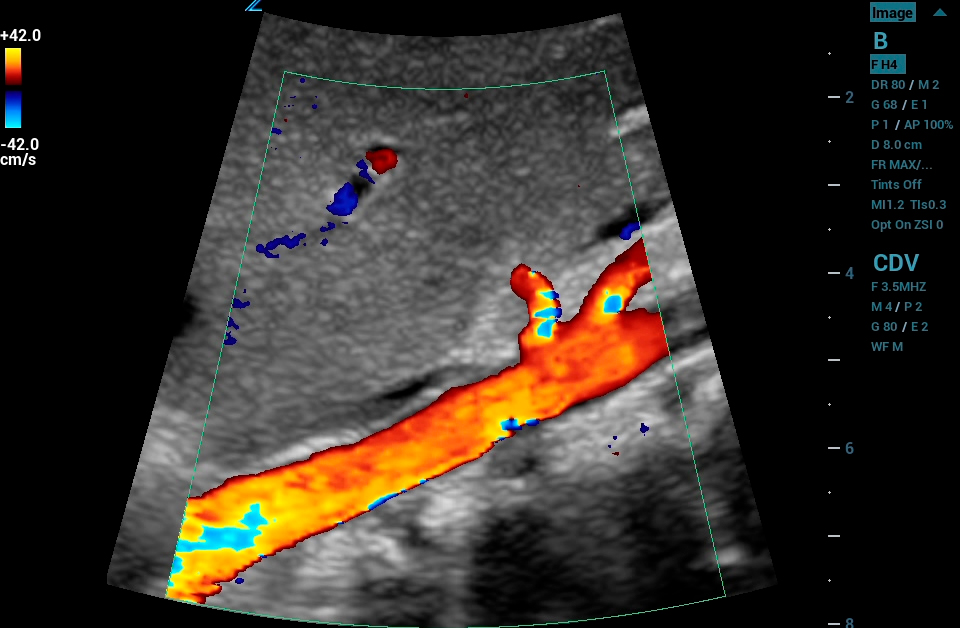

CEUS

Contrast Enhanced Ultrasound (CEUS), Mindray’s unique approach to contrast imaging, allows clinicians to obtain the information needed with a lower dose of the contrast agent. CEUS is now available on all imaging transducers (1-20MHz).